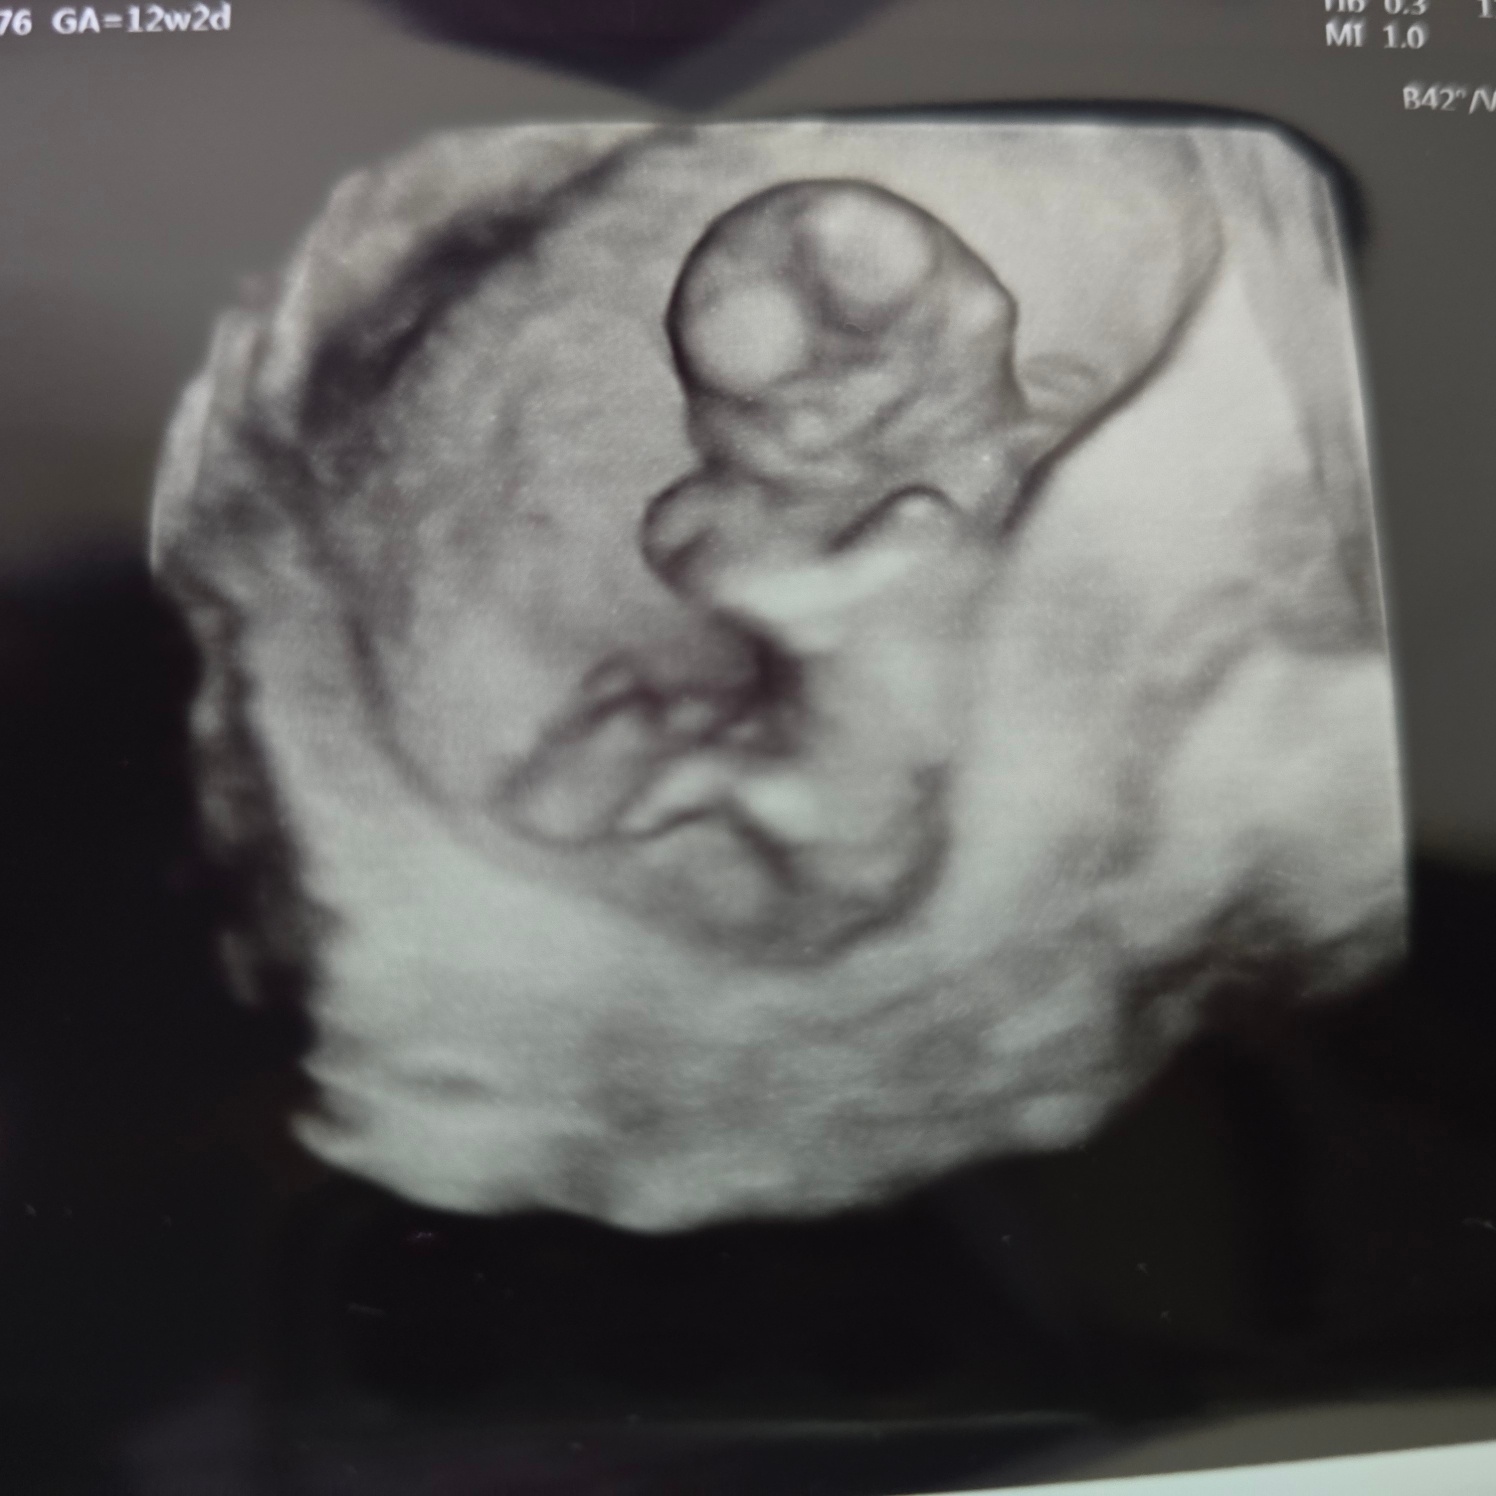

12주 2일 차 - 출산병원으로 옮기고 첫 배초음파!

난임병원에선 계속 질초음파로 봤는데 이젠 아기가 좀 커서 배초음파로 볼 수 있다고 한다!

뚝딱이는 12주 2일 크기로 다 따라잡았다!!! 너무 이쁘고 기특한 뚝딱이!!><

12주 차에 가서 처음으로 배초음파도 보고 입체 초음파도 봤다.ㅎㅎ

배를 정말 세게 누르면서 보던 입체초음파..

꾹꾹 누르시니 배에 힘이 들어가서 욱하면 선생님께선 힘 풀라고 하신다.

배를 그리 꾹꾹 누르시니 아픈걸요..?ㅜㅜ

아기가 모습을 잘 안 보여준다며 이리저리 꾹꾹 누르며 입체초음파를 봤다.

보면서 목 투명대도 확인하고 니프티검사도 신청해서 피도 뽑고 왔다.ㅎㅎ

목투명대는 0.8로 좋다고 하셨다.ㅎㅎ